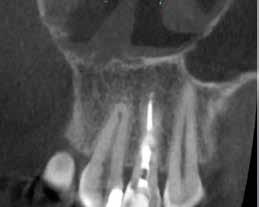

A kezelés befejezését követően 30 hónappal készített CBCT-felvételen a gyógyulás jelei észlelhetők.

A gyökértömés elkészítése során meleg vertikális kompakciós technikát alkalmaztunk, sealerként pedig CeraSeal-t (Meta Biomed; 3. ábra) használtunk. A reszorbciós üreget Biodentine-nel (Septodont; 4. a–b ábra) töltöttük fel. A reszorbcióval érintett területtől koronális irányba elhelyezkedő csatornaszakaszt pedig tisztán meleg guttaperchával kezeltük. Ezt követően a lebenyszéleket visszafektettük, és varratok behelyezésével eredeti pozíciójuknak megfelelően rögzítettük. A koronai részt kompozit tömőanyag segítségével állítottuk helyre. Kontrollvizsgálatra 5, illetve 30 hónappal később került sor (5. ábra). A csontos telődés jelei már 5 hónap után észlelhetők voltak (6. a–c ábra). A 30 hónappal később végzett kontroll során sem találtunk csontban lévő lézióra, törésre vagy egyéb pathológiás elváltozásra utaló jeleket (7. a–b ábra)

MTA-val (Mineral Trioxide Aggregate; Harvard Dental) töltöttük fel. A léziótól koronális irányban elhelyezkedő gyökércsatorna-szakaszt meleg guttaperchával zártuk, majd az MTA-val kitöltött üregre egy kis darab kollagénszivacsot helyeztünk és a lebenyt varratok segítségével eredeti pozíciójában rögzítettük (12. a–b; 13. a–b. ábra). A fog koronai részét Gradia kompozit tömőanyaggal állítottuk helyre (GC; 14. a–b; 15. ábra). Kontrollvizsgálatra két (16. a–b ábra) és négy évvel (17. a–b ábra) később került sor. A kontrollfelvételeken a bukkális kortikális jelenléte volt észlelhető. A fog körüli parodoncium egészséges volt, valamint a páciens sem számolt be tünetekről.

16. a–b ábrák: A két évvel később készített kontroll CBCT-felvétel. – 17. a–b ábrák: A négy évvel később készített kontroll CBCT-felvétel.